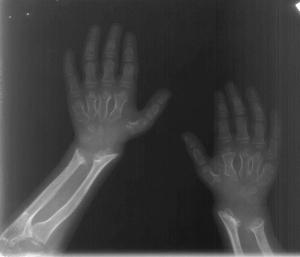

Male child of normal intelligence sent for skeletal survey for coarse facial features, short stature and spinal deformity.